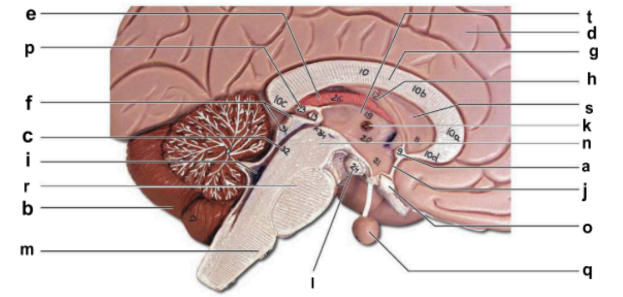

Identify the structure labeled “a” in the image.

anterior commissure

Identify the structure labeled “b” in the image.

cerebellum

Identify the structure labeled “c” in the image.

cerebral aqueduct

Identify the structure labeled “d” in the image.

cerebral hemisphere

Identify the structure labeled “e” in the image.

choroid plexus

Identify the structure labeled “f” in the image.

corpora quadrigemina

Identify the structure labeled “g” in the image.

corpos callosum

Identify the structure labeled “h” in the image.

fornix

Identify the structure labeled “i” in the image.

fourth ventricle

Identify the structure labeled “j” in the image.

hypothalamus

Identify the structure labeled “k” in the image.

interthalamic adhesion

Identify the structure labeled “l” in the image.

mammilary body

Identify the structure labeled “m” in the image.

medulla oblongata

Identify the structure labeled “n” in the image.

midbrain

Identify the structure labeled “o” in the image.

optic chiasma

Identify the structure labeled “p” in the image.

pineal gland

Identify the structure labeled “q” in the image.

pituitary gland

Identify the structure labeled “r” in the image.

pons

Identify the structure labeled “s” in the image.

septum pellucidum

Identify the structure labeled “t” in the image.

thalamus